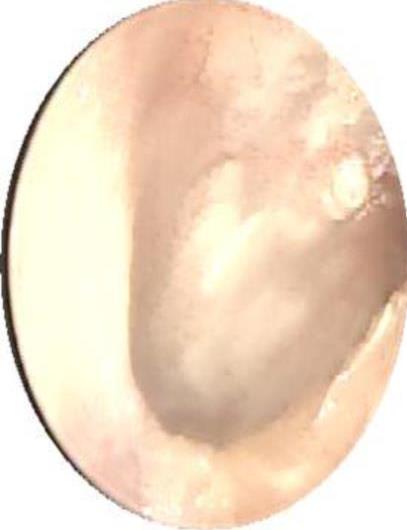

• 医用生物蛋白胶应用于耳内镜下鼓膜修补术的临床疗效

摘要:目的 分析医用生物蛋白胶应用于耳内镜下鼓膜修补术的临床疗效。方法 回顾性分析2022年10月-2023年10月该院收治的60例单纯鼓膜穿孔患者的临床资料,根据手术方法不同,将患者分为研究组和对照组,各30例。研究组术中使用医用生物蛋白胶粘合残余鼓膜和修补材料;对照组术中采用明胶海绵覆盖修补鼓膜。观察两组患者术后的鼓膜愈合情况(鼓膜愈合率、愈合时间、干耳时间和外耳道上下径)和并发症发生情况;于手术前后,采用纯音测听法(500、1 000、2 000、4 000 Hz),测量两组患者气导阈值,观察听力改善程度;采用视觉模拟评分法(VAS)评分,评估患者术后疼痛程度。结果 两组患者术后鼓膜愈合率、愈合时间、外耳道上下径和并发症发生率比较,差异均无统计学意义(P > 0.05)。研究组术后平均气导听阈明显低于对照组,差异有统计学意义(P < 0.05)。研究组术后干耳时间短于对照组,术后第1天疼痛VAS评分明显低于对照组,差异均有统计学意义(P < 0.05)。结论 医用生物蛋白胶应用于耳内镜下鼓膜修补术,可有效地降低气导听阈,缩短干耳时间,减轻患者疼痛,且不增加并发症发生率,值得临床推广应用。